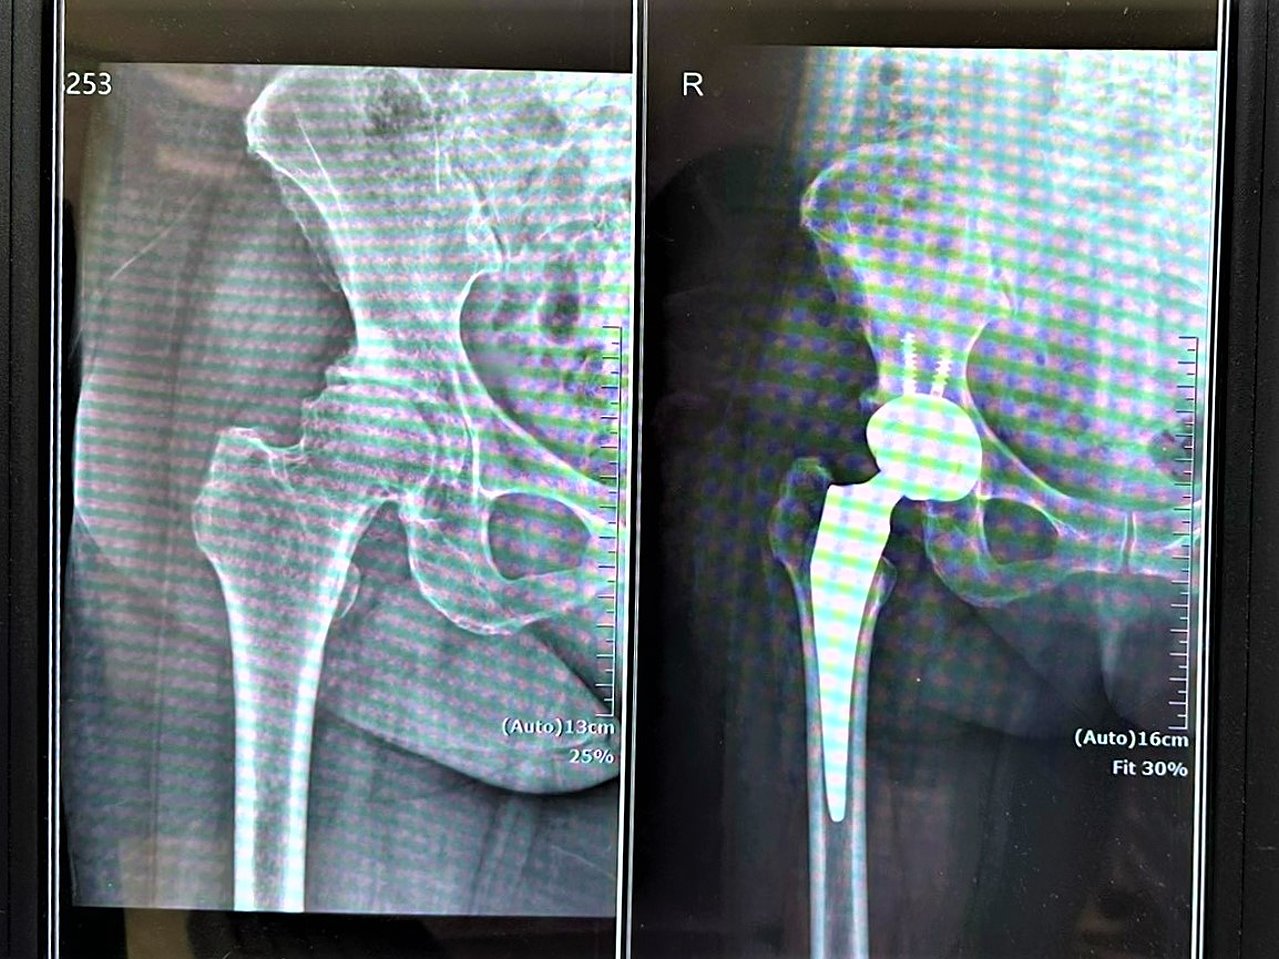

賴醫師指出,正前開人工髖關節置換術如同「撥開門簾進入室內,而非拆門而入」,因肌肉與肌腱得以完整保留,患者在術後初期即可感受到行動負擔減輕,對於提升復原速度與生活品質具有明顯助益,此外,正前開手術在精準度上也具優勢。醫師透過術中 X 光即時導引,確保人工關節置放於最佳位置,有效降低術後出現長短腳的風險。由於周邊肌肉包覆良好,患者術後對於姿勢與動作的限制相對較少,更有利於回歸日常生活。